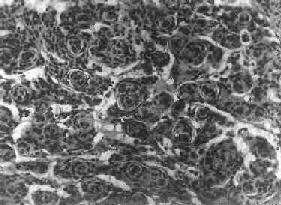

镜下,细胞大小形态一致,呈梭形或胡萝卜形,胞核圆或椭圆,染色质呈细颗粒状,核膜清楚,有核仁。细胞胞浆丰富,突起明显。细胞的排列有二种特征,一是环绕空腔排列成腺管状,形态上与室管膜腔相似,称为菊形团形成,另一是环绕血管形成假菊形团结构,细胞有细长的胞浆突起与血管壁相连(图16-25)。细胞中有神经胶质纤维,以PTAH染色在个别细胞的腔面或胞核旁可见纤毛体,后者与纤毛运动有关,是室管膜细胞的特征性结构。此外,有时还可形成乳头状结构。发生在脊髓圆锥和终丝的肿,乳头状结构轴心中的结缔组织往往富含粘液。

图16-25 室管膜

细胞为圆形或卵圆形,核染色质丰富,胞浆少,可见有细长的胞浆突起与血管相连,呈放射关,形成假菊形团